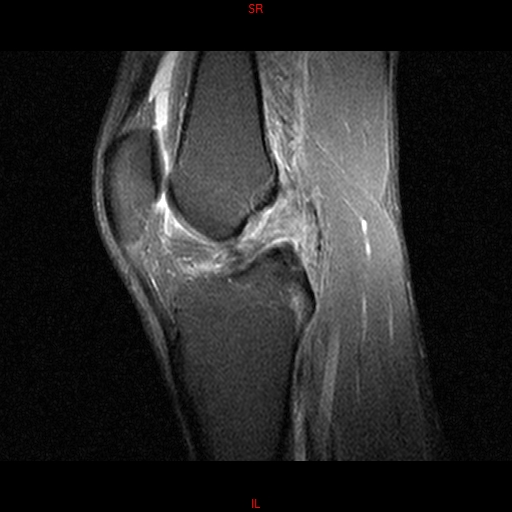

• Resonancia PATOLÓGICA MENISCOPATIA INTERNA DP SAGITAL